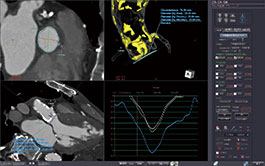

4D TIC

This protocol allows time intensity curves to be generated from one or more ROIs placed anywhere within a multi-phase contrasted volumetric data set. TICs from multiple ROIs can be viewed simultaneously for comparison.